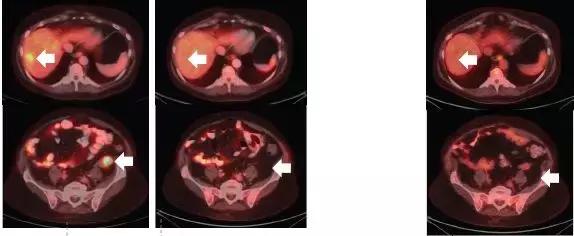

结果十分乐观!

昨天关于第二代TRK靶向药物的论文刚刚发表,最初的两位耐药患者尝试新药后,肿瘤再次快速缩小。比如下面这位,用药一个月后,耐药的肿瘤就再次几乎消失!

耐药后 使用2代药一个月后